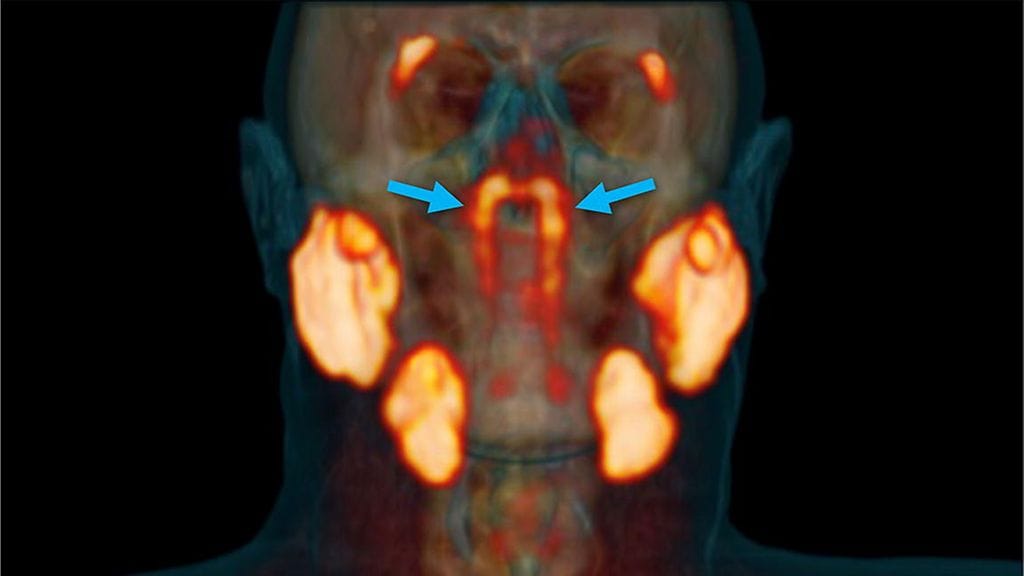

Syvällä nenänielussa – kohdassa, jossa nenäontelo yhdistyy korvatorviin – näyttää sijaitsevan aiemmin tuntematon sylkirauhaspari. Mikäli havainnot vahvistetaan, piilotelleen syljen lähteen tunnistaminen voi olla ensimmäinen laatuaan noin kolmeen vuosisataan, kirjoittaa The New York Times.

Sädehoitojen sivuvaikutuksia pään ja kaulan alueelle tutkineet hollantilaiset syöpätutkijat perehtyivät uudenlaiseen kuvaustapaan, kun he huomasivat yllätyksekseen nenänielun takaosassa kaksi tuntematonta aluetta. Pitkulaisen muotoiset, jopa kuuden senttimetrin pituiset rauhaset vaikuttivat kudosnäytteiden perusteella samanlaisilta kuin tunnetut suuret sylkirauhaset.